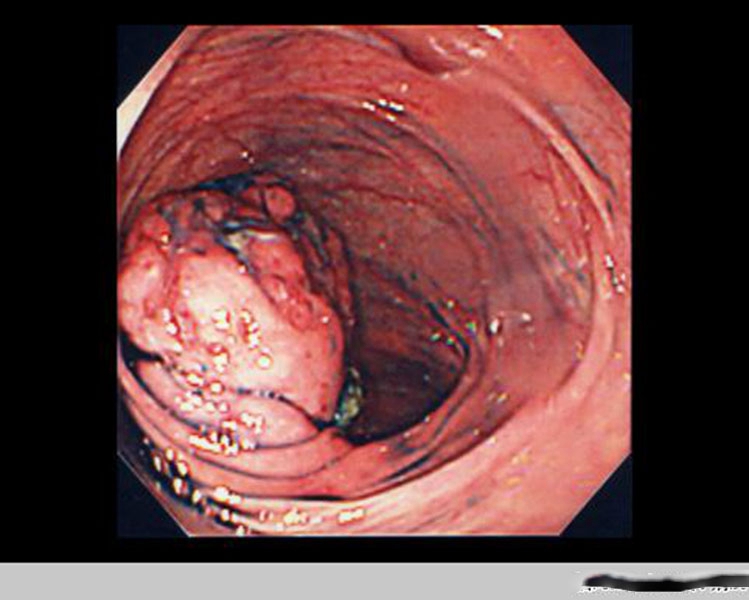

腸腫瘤圖片

腫瘤腸腫瘤切除術

治療腸腫瘤觀察

直腸腸腫瘤手術術後

直腸腸腫瘤手術

直腸腸腫瘤術後

直腸腸腫瘤切除術後